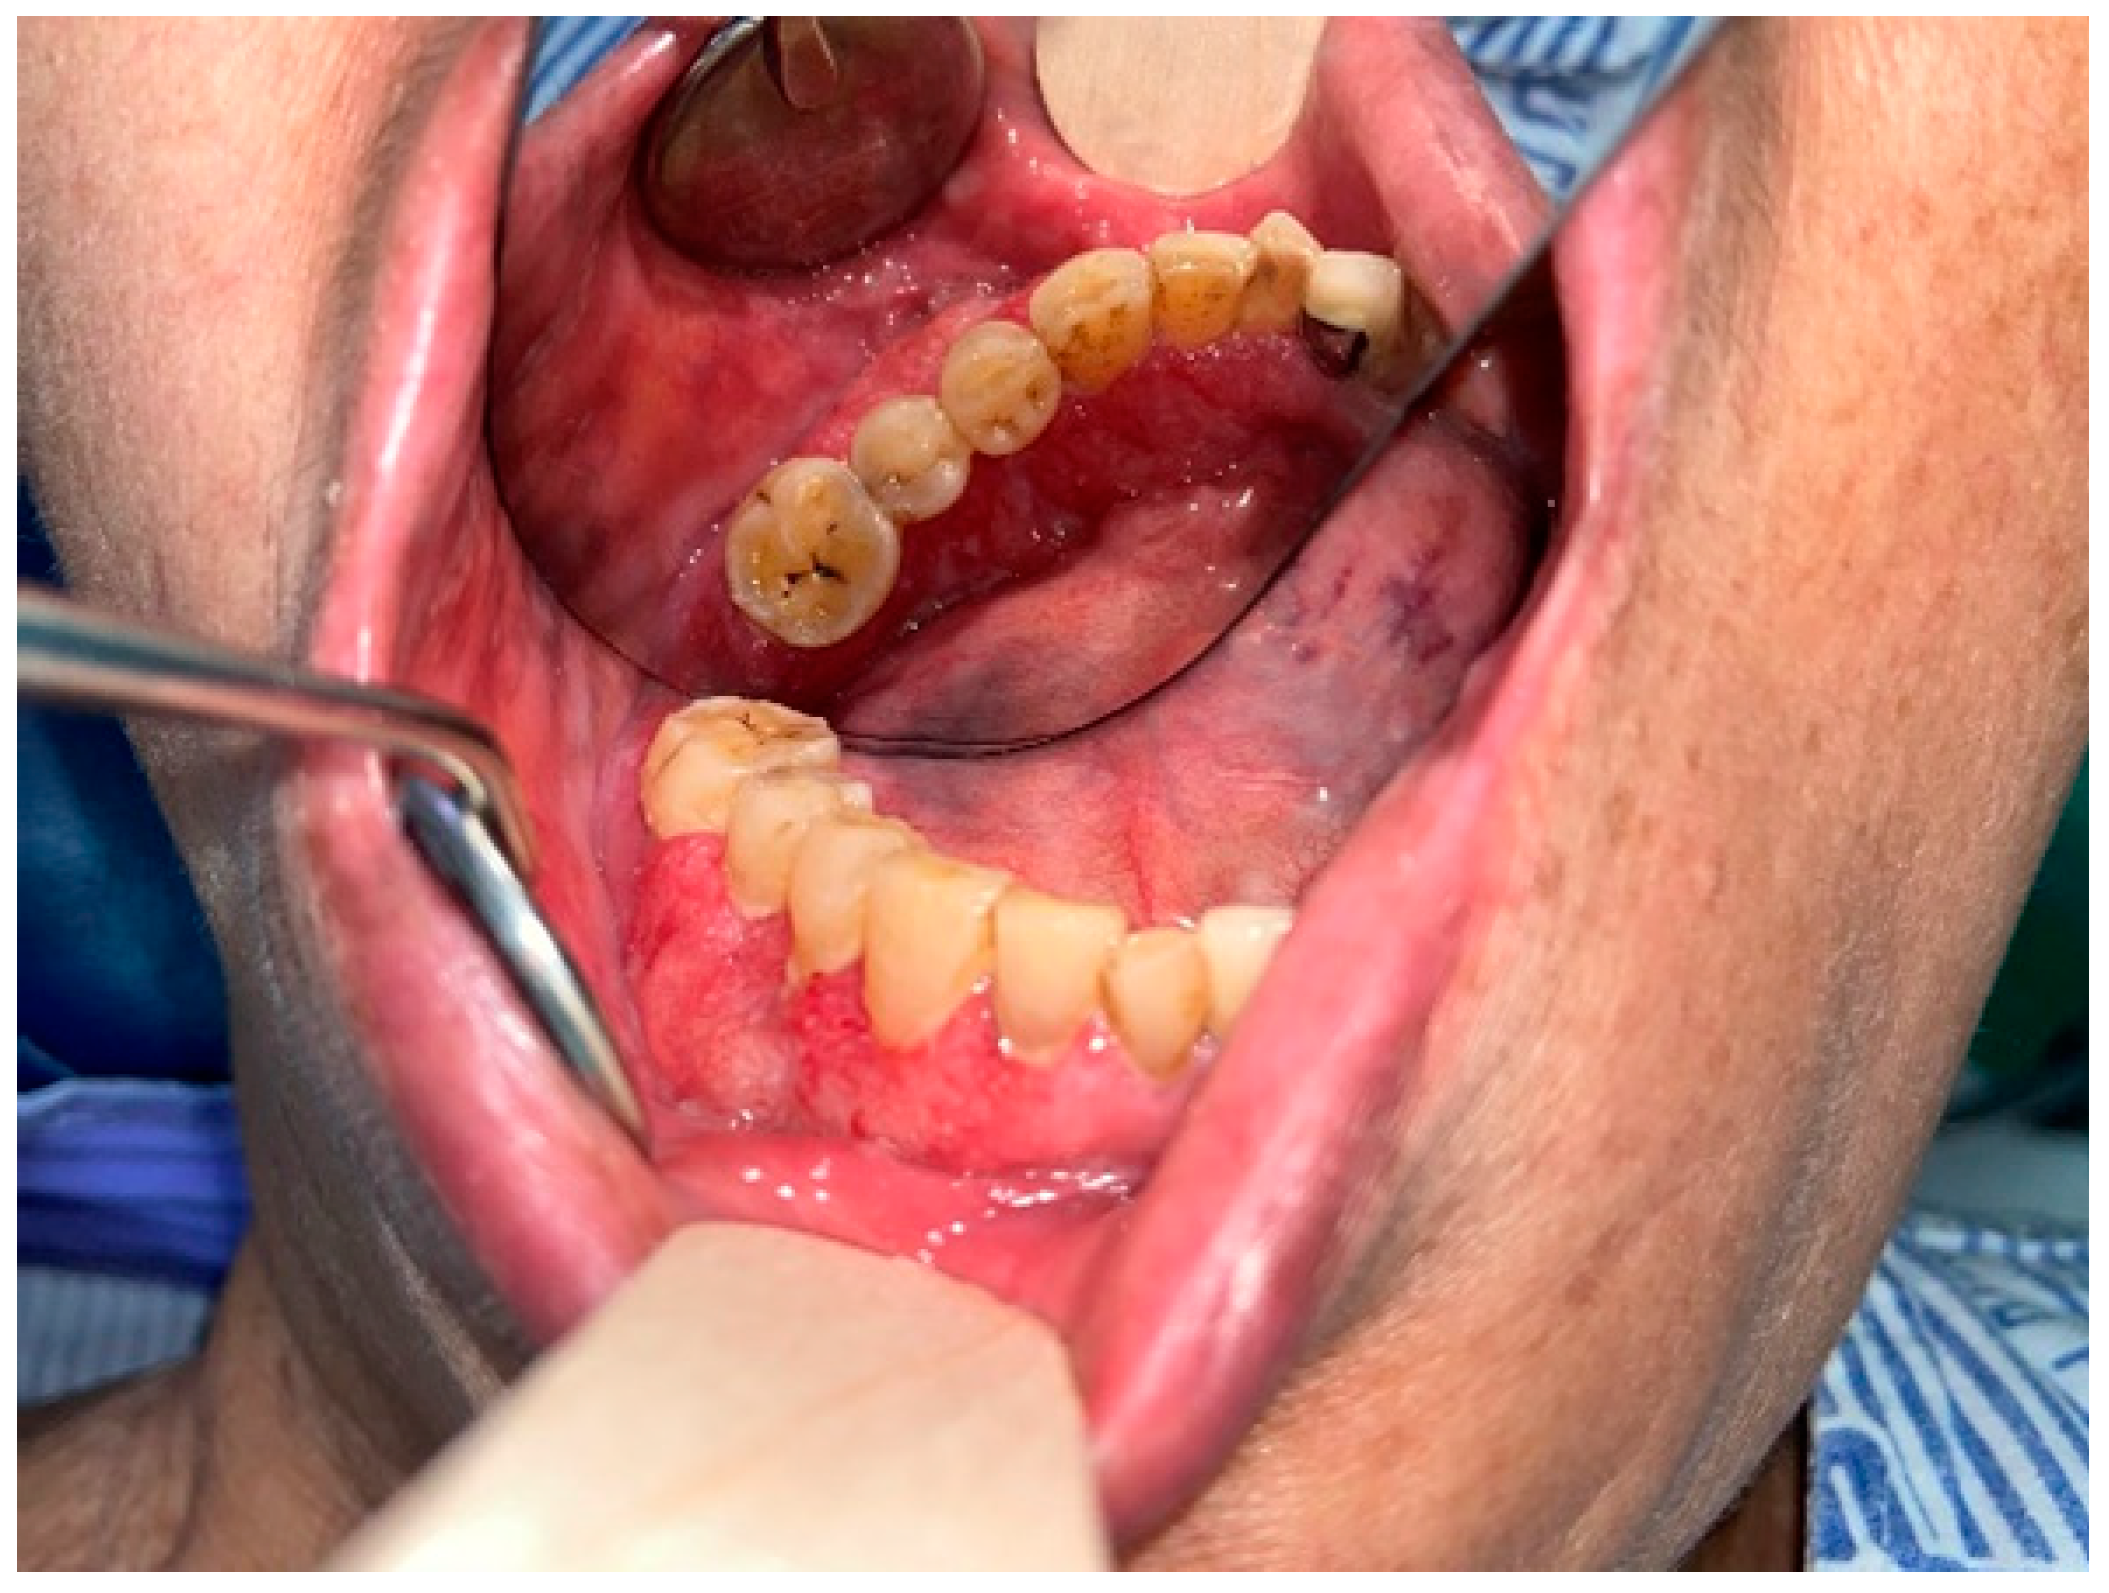

2. Case Report